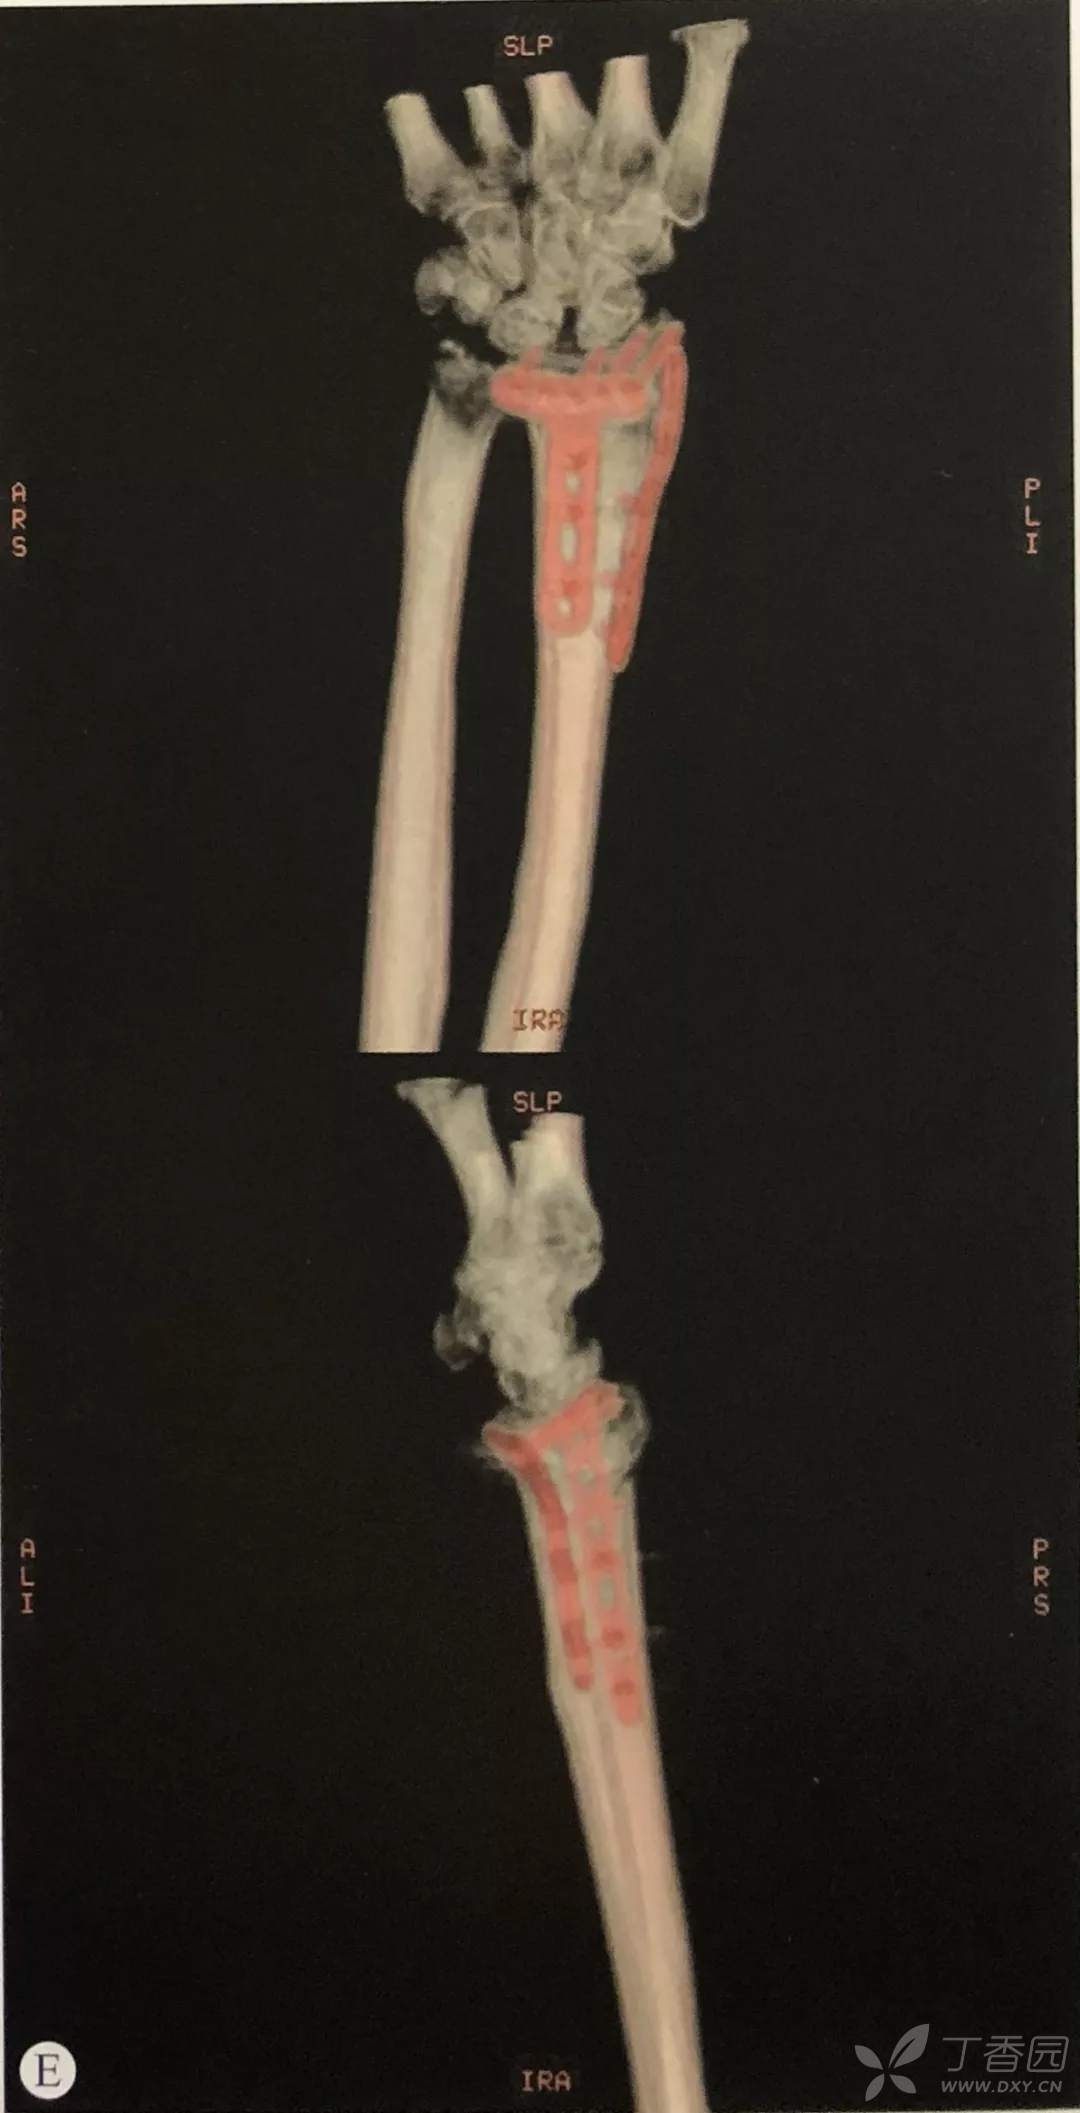

- 采取前述方法复位后,应用锁定钢板进行固定;

- 钢板应尽量靠近关节面放置,以使远端螺钉位于软骨下骨内,提供良好的力学支撑,对于骨质疏松患者,这点尤为重要;

应用第二代、第三代掌侧桡骨远端钢板,可以置入桡骨茎突螺钉固定桡骨茎突骨块。

McQueen等的研究表明,桡骨远端背侧皮质较薄,而关节面下的软骨较为致密,因此钢板应贴近桡骨远端从而使螺钉向背侧远端,使螺钉固定于软骨下骨而非置于背侧皮质。